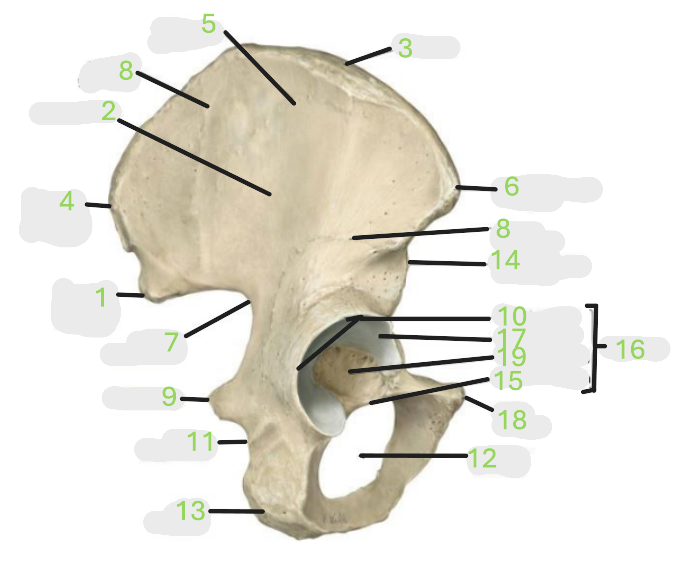

Where is the posterior inferior iliac spine

1

Where is the gluteal surface

2

Where is the iliac crest

3

Where is the posterior superior iliac spine

4

Where is the anterior gluteal line

5

Where is the anterior superior iliac spine

6

Where is the greater sciatic notch

7

Where is the inferior gluteal line

8

Where is the ischial spine

9

Where is the acetabular rim

10

Where is the lesser sciatic notch

11

Where is the obturator foramen

12

Where is the ischial tuberosity

13

Where is the anterior inferior iliac spine

14

Where is the acetabular notch

15

Where is the acetabulum

16

Where is the lunate surface

17

Where is the pubic tubercle

18

Where is the acetabular fossa

19